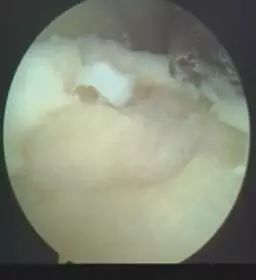

踝关节“反复扭伤”是踝关节不稳的一种表现,也是一种疾病,必须得到重视。长期的踝关节不稳及反复扭伤,造成踝关节的受力不平衡,可以引起关节内的一系列病理变化,容易出现踝关节软骨的损伤(常见是距骨骨软骨损伤,见图示),加快踝关节的退行性病变,增加治疗的难度,影响治疗的效果。